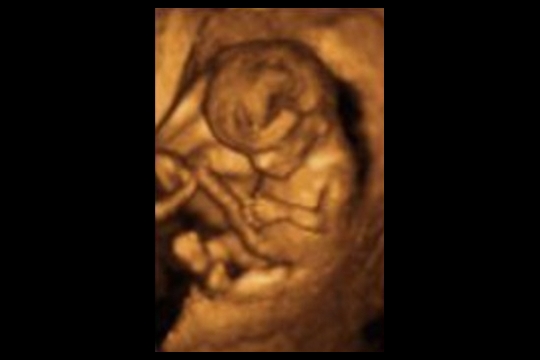

Corte sagital